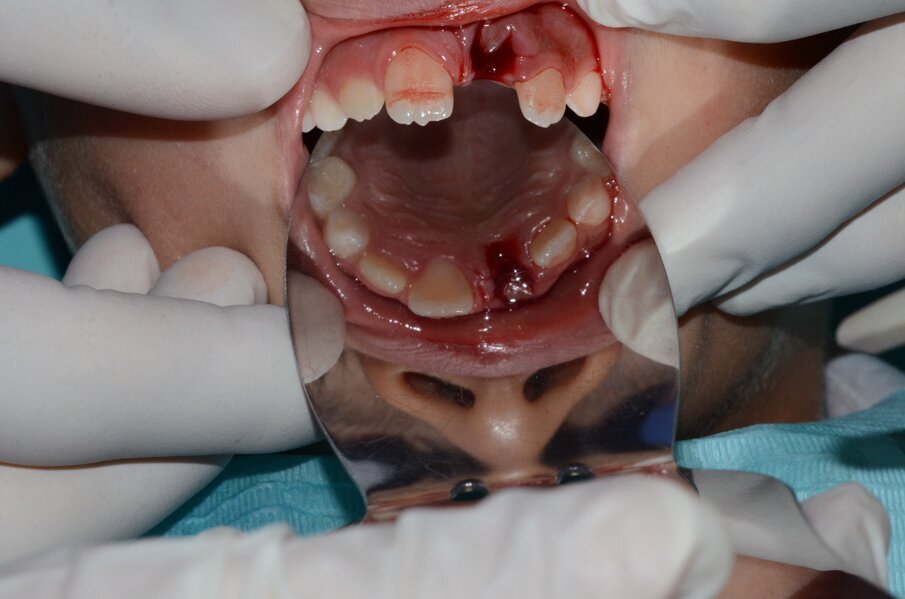

An 8-year old child presented to the department of paediatric dentistry at the Hamdan Bin Mohammed College of Dental Medicine (HBMCDM) at the Mohammed Bin Rashid University (MBRU) in Dubai Healthcare City. He allegedly fell off a climbing wall, and knocked out his upper left maxillary incisor (tooth # 21) and cut his lower lip (Figures 1 and 2). This occurred at 14:15 hours at school, and the school nurse called the patient’s mother at 14:20 hours. The patient’s mother asked the nurse to find the tooth and put it in milk. The tooth’s “dry time” was thus around 10 minutes. The patient attended with both his mother and aunt, to our specialist clinic at 14:55 hours.

• 21: empty socket with coagulum.

• Laceration of the buccal gingiva near 21.

After the patient’s initial assessment, we administered LA to his upper anterior sextant and lower lip. During this time, both the tooth and socket were gently irrigated with physiological saline. 21 was found to have an immature root and open apex. (Figures 5 a & b).

Figure 2: Palatal view of 21 socket. Notice the coagulum filled socket

Figure 6: Tooth 21 was replanted gently into the socket after giving LA. This took place 60 minutes after the injury

Figure 7. A passive composite and wire splint involved # 12 to 22. The lip was yet unsutured.